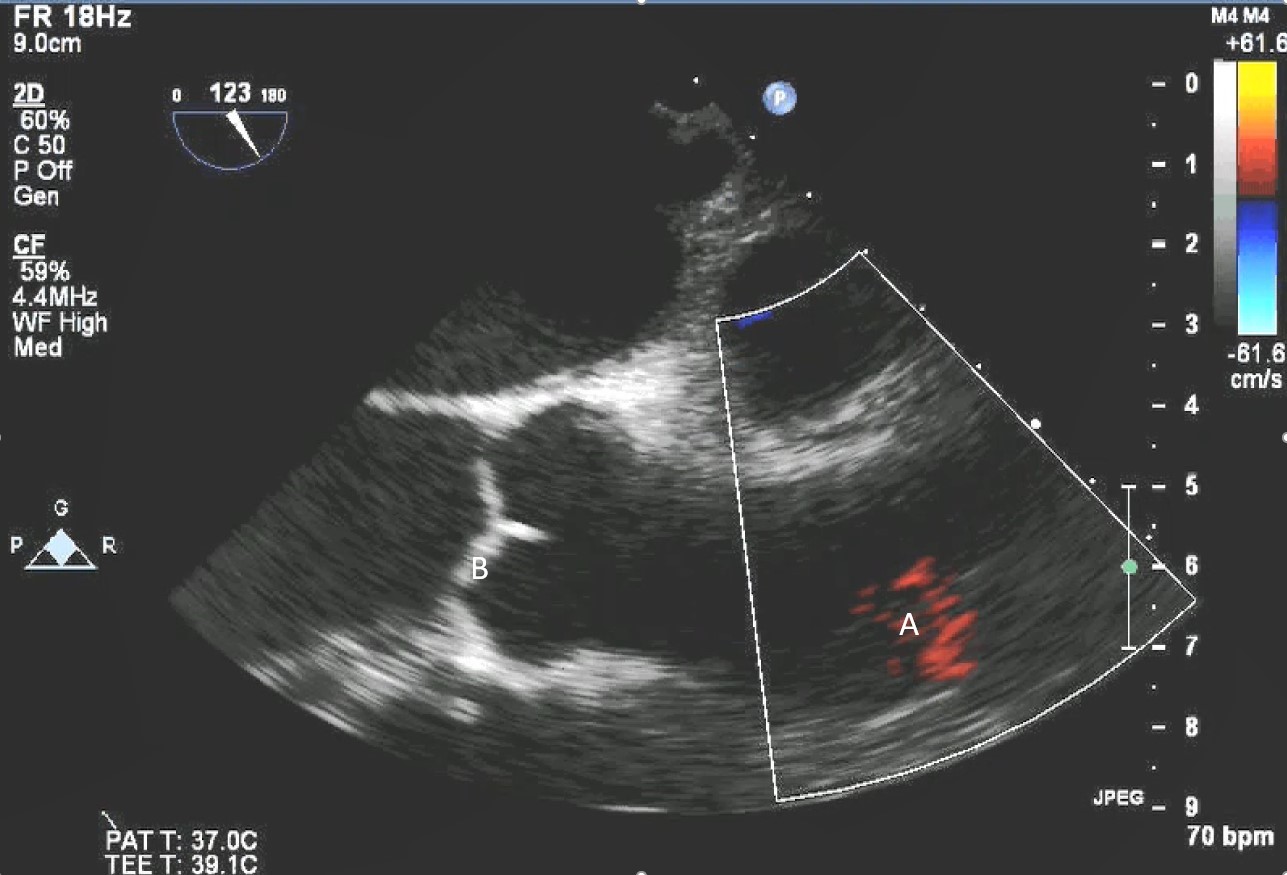

After initial access is obtained with a guidewire, TEE can confirm placement of the guidewire within the aorta and ensure there is no iatrogenic dissection from the procedure. The midesophageal long axis and 4 chamber views can be used to visualize the guidewire crossing of the aortic valve and positioning within the LV cavity. The wire tip should point towards the LV apex. Wire placement too deep within the LV can trigger ventricular arrhythmias and tethering of the mitral valve or subvalvular apparatus should be avoided as this can result in the inlet abutting the mitral valve or damage to subvalvular apparatus (Figs. 3,4) [13]. When the proceduralist is advancing the Impella over the guidewire, the best view to observe the device crossing the aortic valve is the midesophageal long axis view [13].

Impella (A) in the LV cavity caused disruption and damage to subvalvular apparatus resulting in flail segment (B) of the mitral valve.

Fig. 4.Impella (A) placement causing disruption and damage to subvalvular apparatus resulting in mitral valve flail (B) and mitral regurgitation (C).